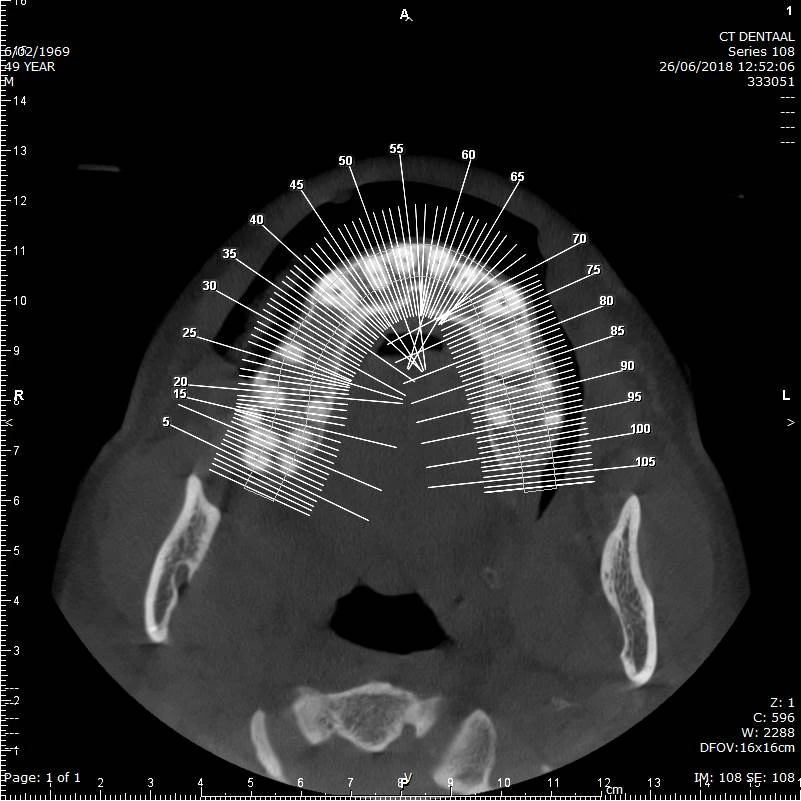

CBCT voorbeeld 2: axiale doorsnede

Axiale doorsnede: overzicht van de tandenboog en projecties